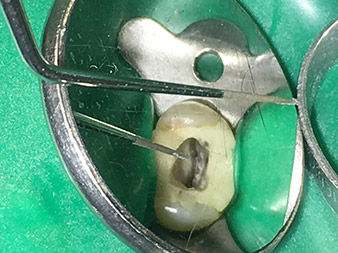

Атравматична препарация на пода на кавитета с накрайник 4Е.

Накрайник 4Е – този накрайник е изключително подходящ за подготовка на пода на кавитета при прехода към каналите. Той може да се използва за оптимално заглаждане на прехода между канала и пода на кавитета, така че да се получи фуния, водеща в канала. Освен това, инструментът е идеален избор за премахване на калцификати от каналите.

Като цяло, кавитетът може да бъде подготвен много ефективно и минимално инвазивно с този накрайник чрез заглаждане на калцификати, ъгли и ръбове.